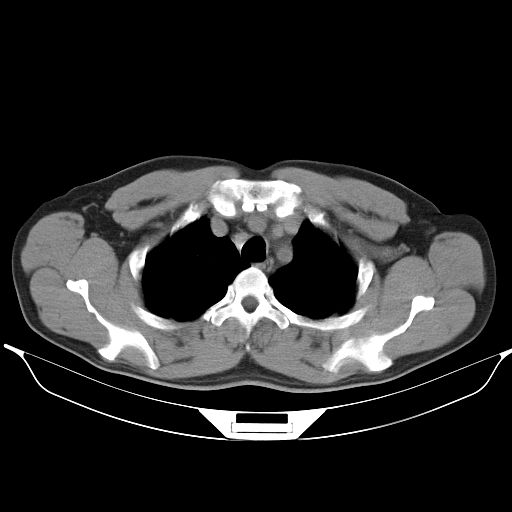

标题: CT25490:男,40岁,体检发现;无其它不适。 [打印本页]

标题: CT25490:男,40岁,体检发现;无其它不适。

考虑右下肺周围性肺癌并肺内多发转移,纵隔淋巴结转移!

支持 !考虑右下肺周围性肺癌并肺内多发转移,纵隔淋巴结转移,(气管前腔静脉后,隆突下,主动脉弓下都有了)